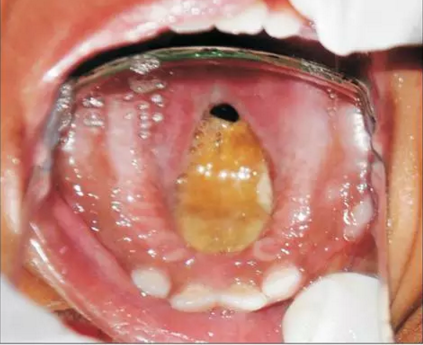

患者為18個月齡的幼兒,主訴為口腔上腭大面積潰瘍伴鼻腔反流及口腔異味。患兒1個月前曾在外院治療過肺炎,治療過后一個月,患兒家長發(fā)現患兒上腭出現一小潰瘍并再一次就診。潰瘍在三天內顯著增大并導致上腭穿孔?;純撼霈F吞咽困難及鼻腔反流等癥狀。為求治療穿孔及相關癥狀及預防吸入性肺炎來我院就診。患兒沒有糖尿病、惡性血液病等病史,也沒有鼻竇炎或流涕等癥狀??趦葯z查發(fā)現上腭一暴露骨面的巨大潰瘍,范圍從腭中縫至軟腭,局部穿孔?;純嚎诘?、舌、頰粘膜、唇、鼻中隔皆正常,上頜乳切牙、乳側切牙、左下頜第一乳磨牙已萌出。